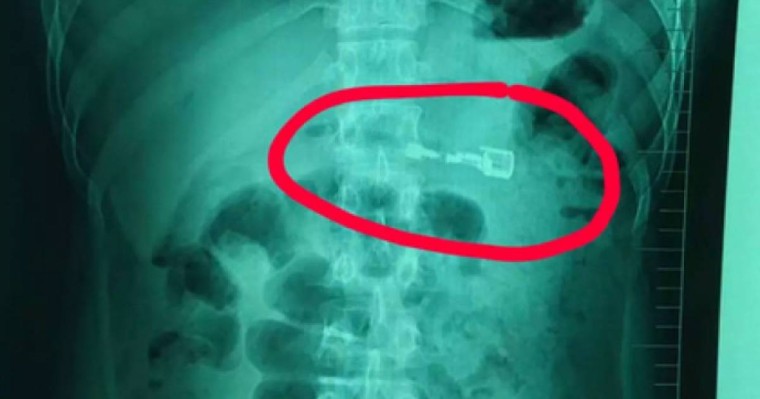

Қытайда дәрігерлер ер жігіттің асқазанынан газбен жанатын кәдімгі оттықты шығарып алды. Бұл туралы WeChat әлеуметтік желісіне 12 наурызда Ляонин провинциясындағы Шеньян қаласының ауруханасы өкілдері жеткізген, деп хабарлайды Zakon Lenta.ru-ға сілтеме жасап.

Жексенбіде, 10 наурыз күні таңертең бала жергілікті ауруханаға жеткізілді. Пациентке отау жасау тым қауіпті деп шешкен дәрігерлер Лиді Шэньян қаласындағы ірі ауруханаға жеткізді. Ол жерде пациенттің асқазан қышқылы сегіз сантиметрлік оттықтың пластигін еріте бастағаны анықталған. Оның ішіндегі газ кез-келген сәтте сыртқа шығып кетуі мүмкін екен.

Қауіпті зат Лидің асқазанында 30 сағаттай болған, ендігі алынбаса – жарылып кету қаупі болды. Дәрігерлер "зажигалканы" эндоскоптың көмегімен үш минуттың ішінде шығарып алды.